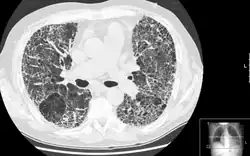

Tomografia computadorizada de extensa fibrose causada por inflamação pulmonar (pneumonite).

A espirometria permite identificar que se trata de uma doença pulmonar restritiva, mas a radiografia(como raio X) do tórax pode não ser suficiente para encontrar cicatrizes nos pulmões, sendo assim recomendado uma tomografia computadorizada de alta resolução para confirmar a presença da fibrose.[3]